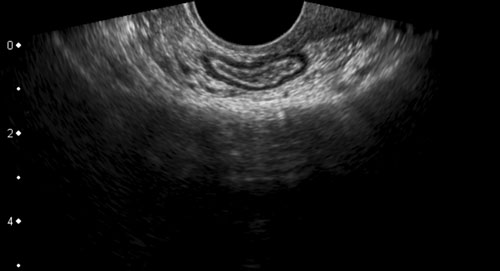

Các ổ lạc nội mạc tử cung trên bề mặt ngoài của đại tràng ở bốn bệnh nhân khác nhau.

Các ổ lạc nội mạc tử cung (*) trong túi cùng Douglas là các khối đặc, giảm âm, kém mạch máu, khu trú không đối xứng, liên tục với lớp cơ giảm âm phía ngoài của đại tràng.

Lớp dưới niêm mạc tăng âm phía trên và niêm mạc đại tràng thường còn nguyên vẹn. Điều này cũng giải thích tại sao máu trong phân khá hiếm gặp trong DIE.

Bờ ngoài của các khối giảm âm này thường dính chặt vào tử cung và/hoặc cổ tử cung. Thường có thể thấy hình ảnh tua gai hoặc “kéo căng” ở các bờ ngoài.

Sự dính vào tử cung và cổ tử cung có thể được chứng minh bằng cách nhẹ nhàng đẩy đầu dò qua lại.

Hình ảnh TVUS của DIE kèm theo bệnh phẩm phẫu thuật.

Ở bệnh nhân này, lớp dưới niêm mạc tăng âm của thành đại tràng sigma mặt trước rõ ràng phủ lên trên ổ lạc nội mạc tử cung lớn (*). Lưu ý thành đại tràng sigma mặt sau hoàn toàn bình thường.

Bệnh phẩm cắt bỏ cho thấy lớp (dưới) niêm mạc (các mũi tên) còn nguyên vẹn và phủ lên trên DIE (*). Đúng như dự đoán, bệnh nhân này cũng không có tiền sử chảy máu trực tràng.